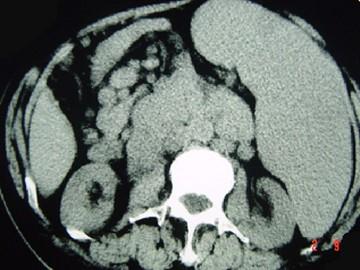

问题 女,30岁,腹痛腹泻、恶心呕吐、皮肤瘙痒,影像检查如图,最佳诊断是()

选项 A.恶性淋巴瘤 B.腹膜后淋巴结核 C.腹膜后转移瘤 D.神经纤维瘤 E.神经鞘瘤

答案 A